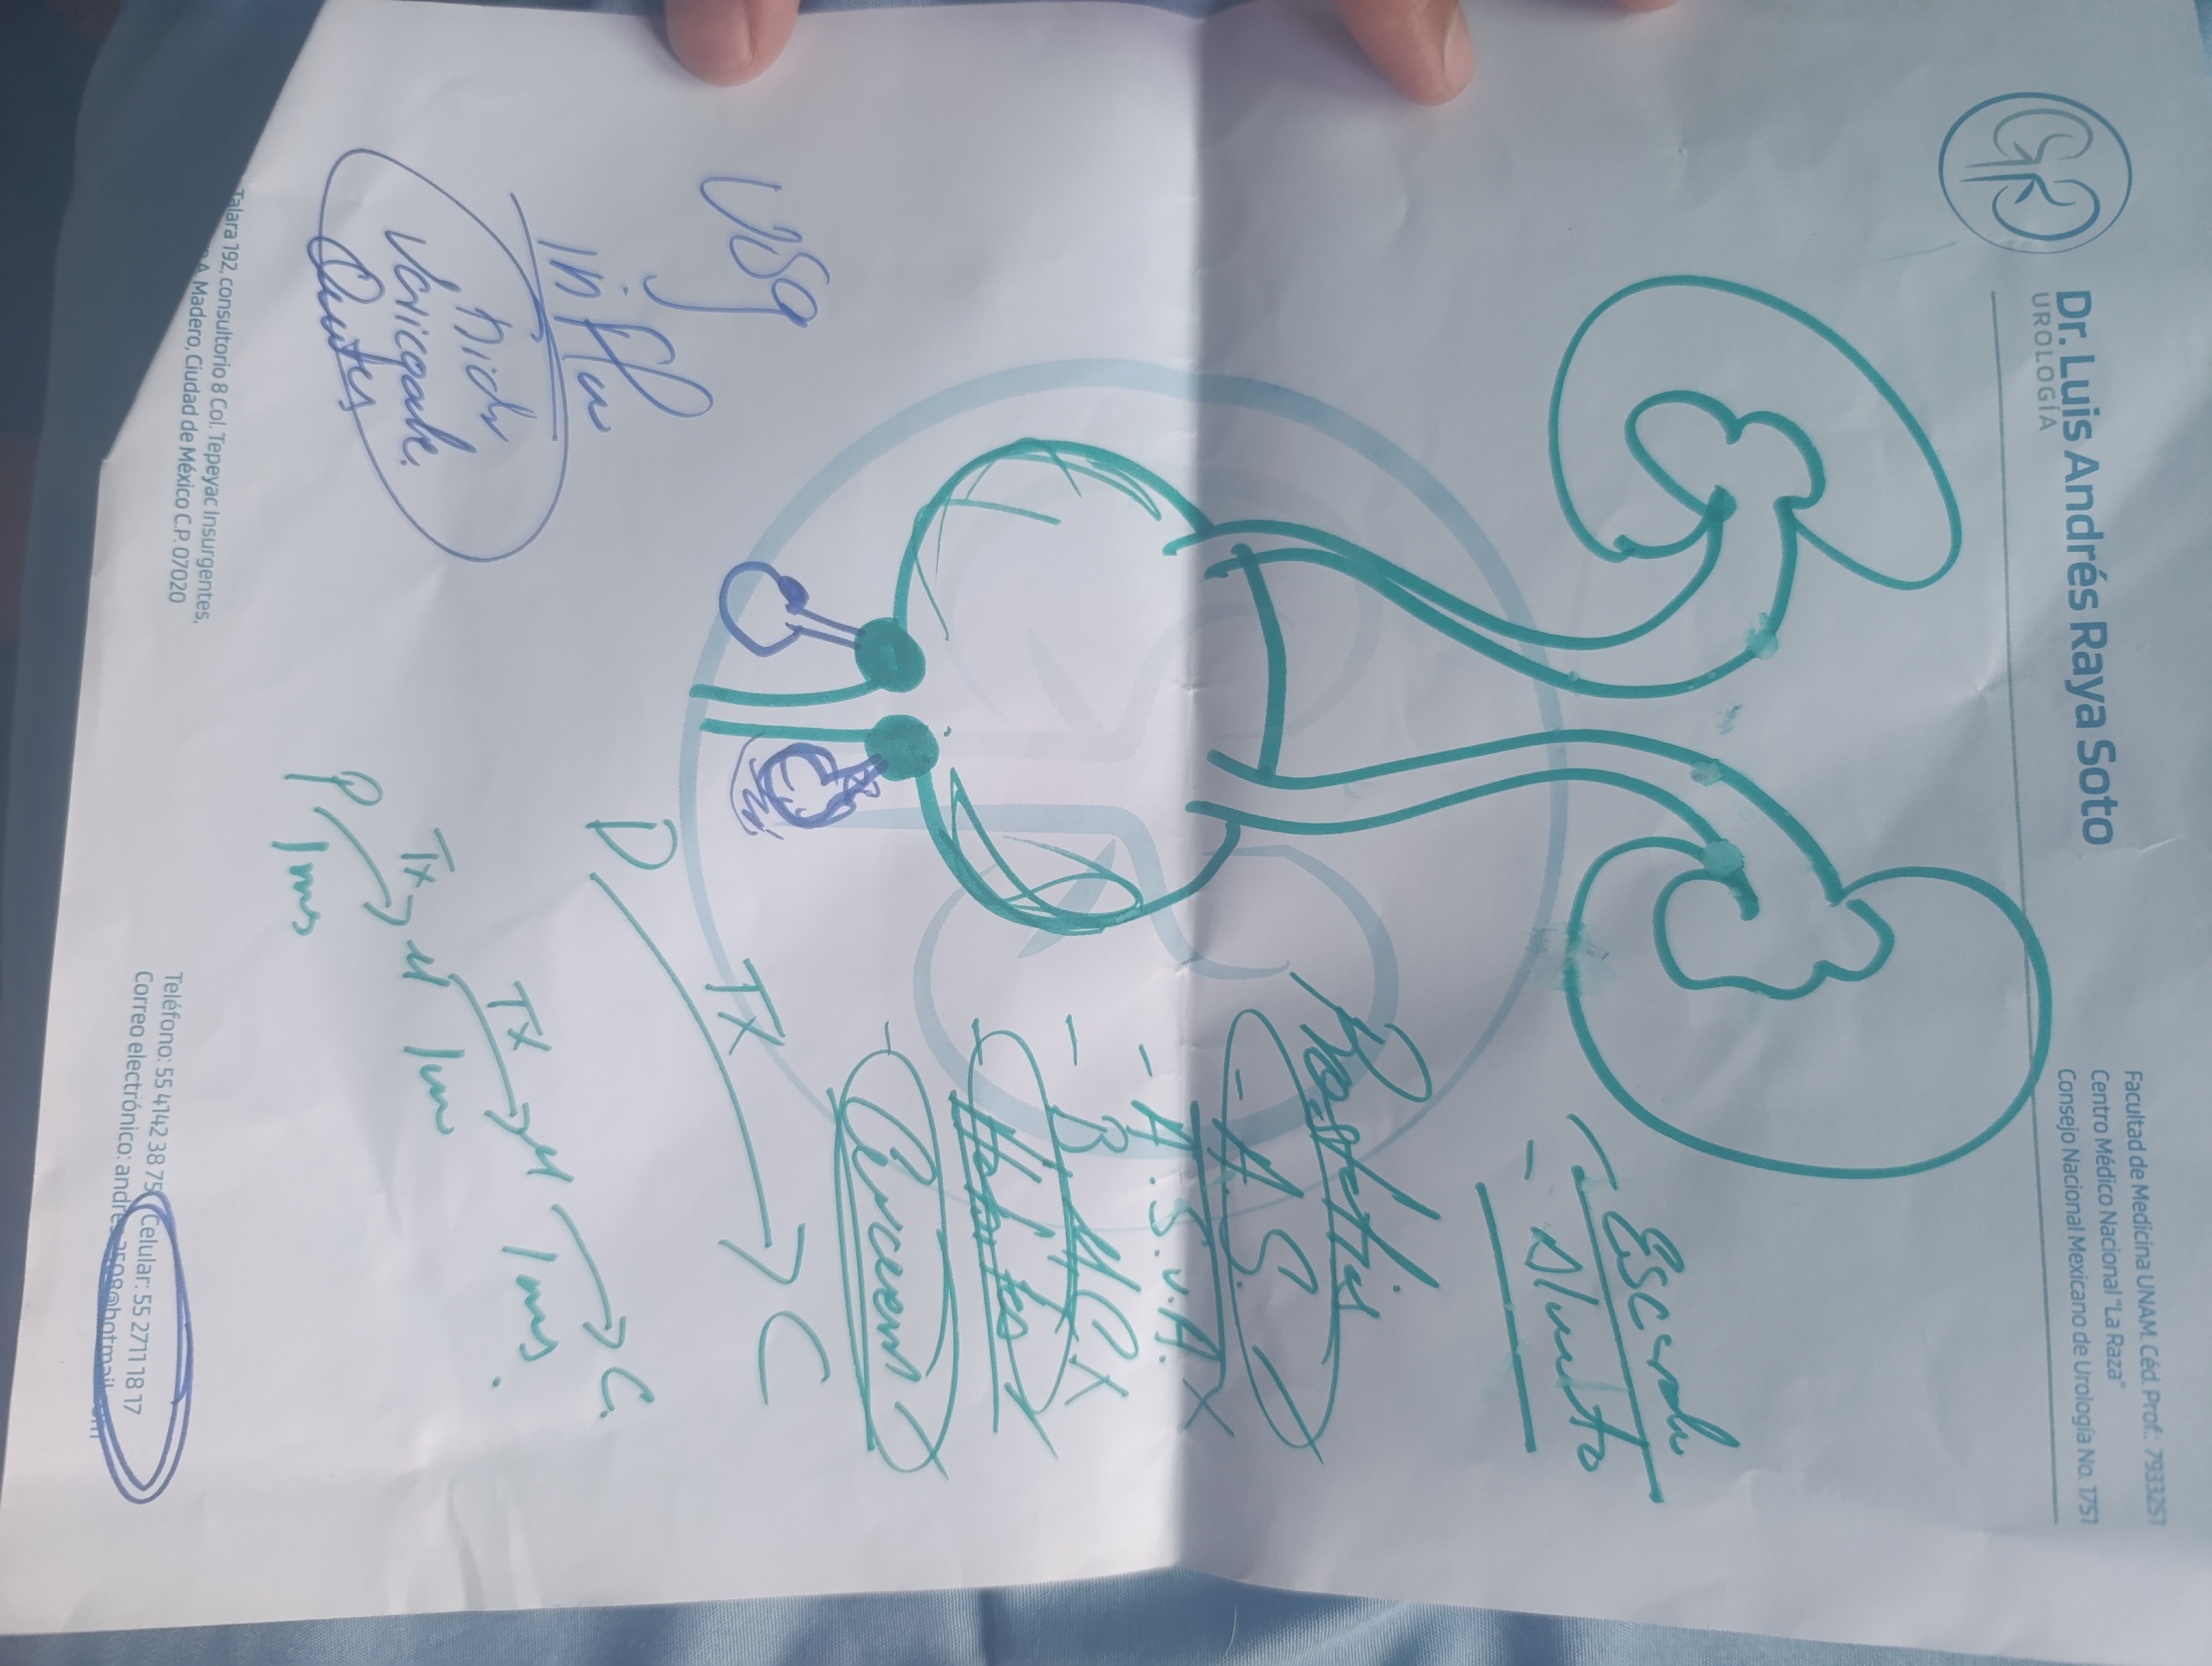

Hola me Llamo Raúl ,tengo 25 años , soy de la CDMX , me atrevo a pedir está ayuda , ya que desde hace unos meses empecé a sentir fuertes dolores en la zona de los testiculos, me hicieron estudios Doppler Testiculares, me detectaron Varicocele de Grado 4 en ambos testículos y microlitiasis testicular en ambos testículos y también tengo hernias en ambos conductos de los testiculos, sufro de fuertes dolores en ambos testículos , eso también está provocando que mi próstata este inflamada, no puedo mantenerme mucho tiempo parado o sentado, me duele mucho al orinar aveces con sangrado, llega el punto en que no puedo ya controlar la orina sale por su cuenta propia, no me atiendo en el IMSS porque el tiempo de espera es mucho , fui a médico particular y me dijeron que ya era urgente la operación porque la sangre no está llegando a los testiculos y se están muriendo, en estos momentos corro riesgo de Esterilidad , y las hernias si no se tratan pueden abrir mas y provocar que los intentos bajen por los conductos de los testiculos y sea una urgencia muy grava y riesgo de una extirpación del intestino si eso llega a pasar , pido su ayuda para poder llegar a esta cantidad, ya que en mi situación es muy difícil poder conseguir todo el dinero.

Usaría el dinero para pagar la operación , y gastos antes y después de la misma . Y poder superar esto que todos los días se vuelve más difícil para mí . Estoy a punto de terminar mi carrera, soy deportista y que este viviendo esto me impide hacer muchas cosas, tengo metas y sueños por cumplir, espero poder contar con la ayuda que me permita salir de esto❤️